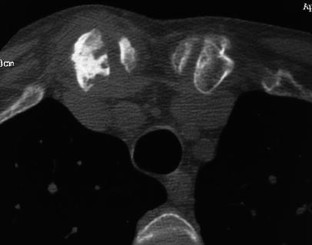

The SAPHO syndrome was a term coined to include a variety of musculoskeletal disorders associated with skin conditions, mainly palmoplantar pustulosis and acne conglobata. It is more correctly a spectrum which includes the following: skin lesions, osteoarticular manifestations of synovitis hyperostosis and osteitis affecting particular target sites, and·a clinical course marked by relapses and remissions. The major sites of involvement are the anterior chest wall, the spine, long bones, flat bones, and large and small joints. The distribution and severity of involvement varies from the adult to the pediatric form of chronic recurrent multifocal osteomyelitis (CRMO). The diagnosis of SAPHO syndrome is not difficult when the typical osteoarticular lesions are located in characteristic target sites. The diagnosis is more difficult if atypical sites are involved and there is no skin disease.

Fig. 6.